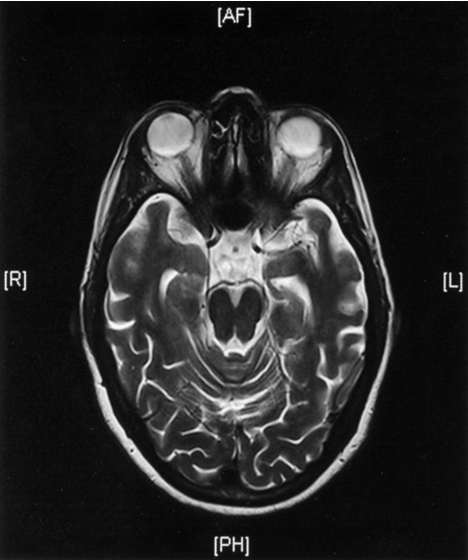

MRI head (T2-weighted; axial plane)

- of a patient with increasing memory disturbance

- Medial temporal lobe atrophy is accompanied by widening of the subarachnoid space and dilatation of the temporal horns of the lateral ventricles

- These changes have been observed in the setting of Alzheimer disease.